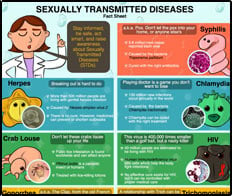

- Products include educational fact cards

- 250 microbes, organs, cells, and health topics

- Educational tools for students and healthcare professionals